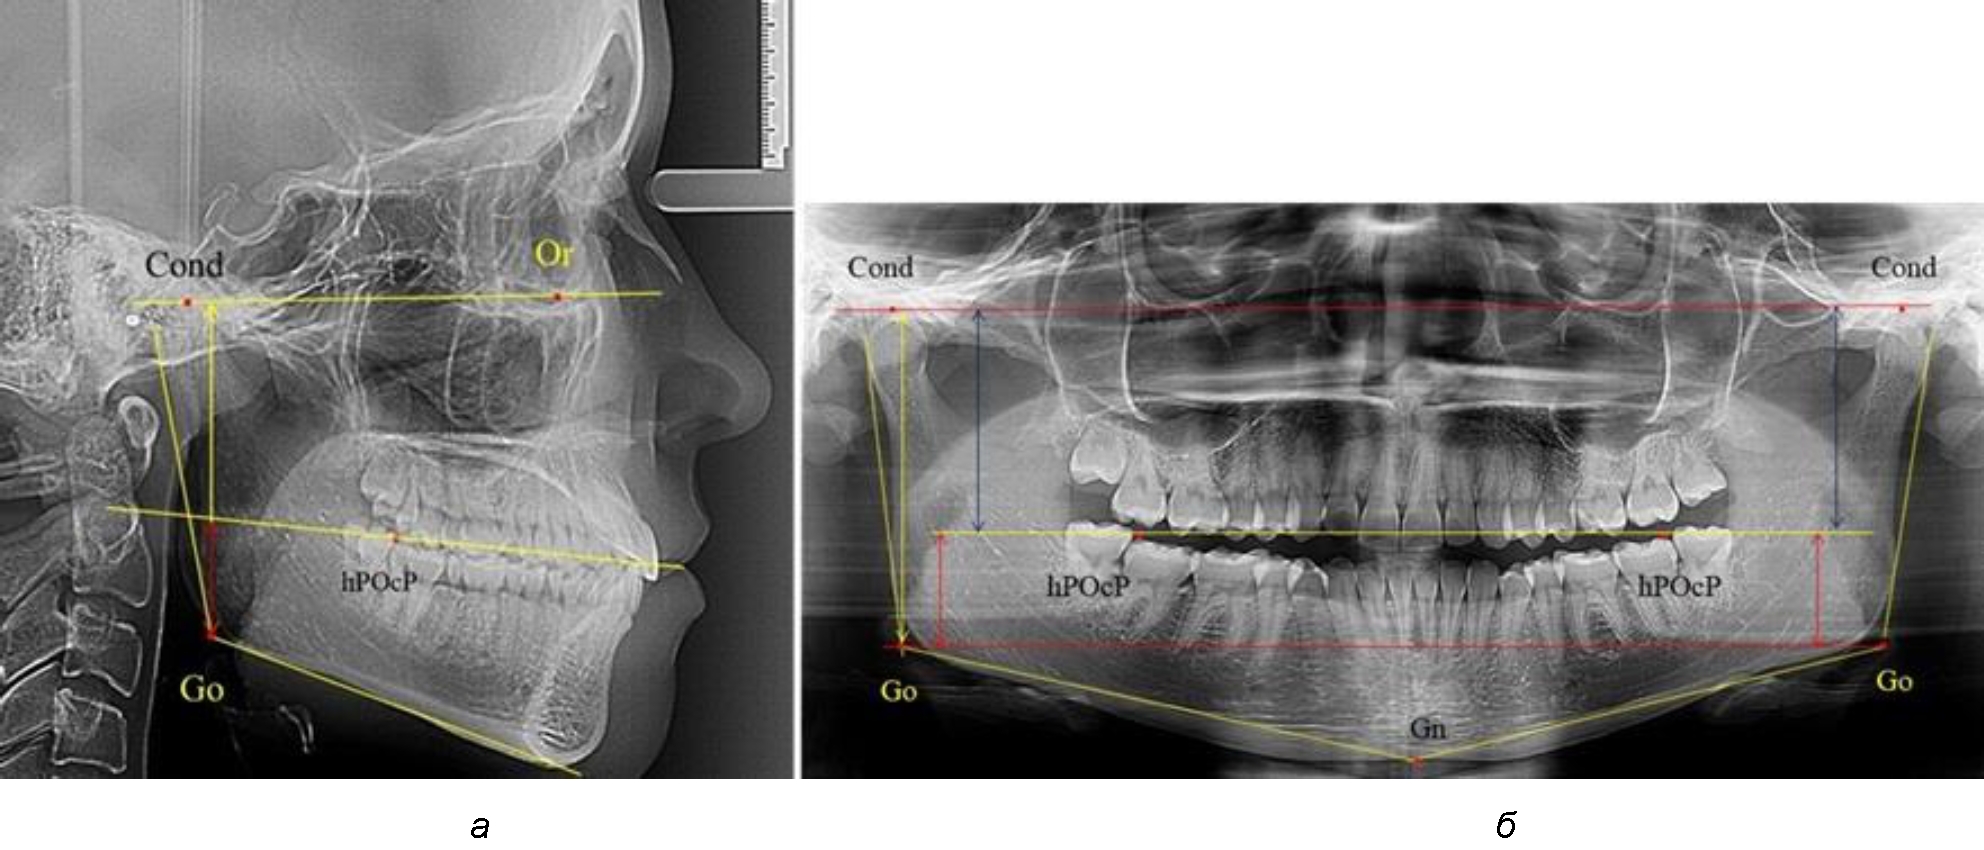

Рис. 1. Метод измерения высоты ветви нижней челюсти на телерентгенограмме (а) и ортопантомограмме (б)

3-я подгруппа была с наименьшим количеством анализируемого материала, и здесь было проанализировано 17 комплектов рентгенограмм [(22,97 ± 4,89) %], на которых средняя величина отношения верхней части ветви к нижней составляла 2,45 ± 0,04, что было достоверно больше показателя, полученного по группе в среднем, а также в 1-й и 2-й подгруппе. Визуально параметры ветви отличались от других подгрупп. Высота ветви составляла (57,83 ± 0,89) мм, что было несколько меньше, чем в других подгруппах. Максимальная высота была 64 мм, а минимальная – 53 мм. Высота верхней части составляла (41,03 ± 0,59) мм, что было близким по значениям, полученным в других подгруппах и свидетельствовало о меньшей вариабельности указанного параметра. В то же время высота нижнего отдела ветви была (16,83 ± 0,36) мм и показатель отличался в меньшую сторону, по сравнению с аналогичным размеров в других подгруппах (рис. 4).

Рис. 4. ОПТГ пациента 3-й группы с увеличенным коэффициентом соотношения частей ветви нижней челюсти